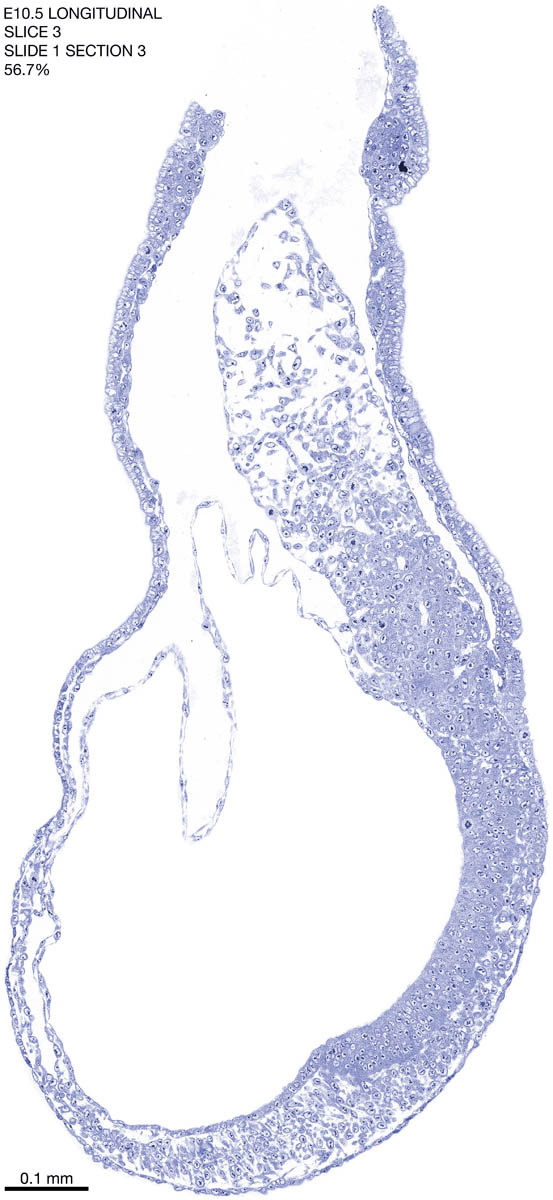

E10.5 Longitudianal Archive This page contains jpg files of ALL SLICES (each 3µm thick) that were scanned of the E10.5 longitudinally cut specimen. Download: Large | High Res Download: Large | High Res Download: Large | High Res Download: Large | High Res Download: Large | High Res Download: Large | High Res Download: Large | High Res Download: Large | High Res Download: Large | High Res Download: Large | High Res Download: Large | High Res Download: Large | High Res Download: Large | High Res Download: Large | High Res Download: Large | High Res Download: Large | High Res Download: Large | High Res Download: Large | High Res Download: Large | High Res Download: Large | High Res Download: Large | High Res Download: Large | High Res Download: Large | High Res Download: Large | High Res Download: Large | High Res Download: Large | High Res Download: Large | High Res Download: Large | High Res Download: Large | High Res Download: Large | High Res Download: Large | High Res Download: Large | High Res Download: Large | High Res Download: Large | High Res Download: Large | High Res Download: Large | High Res Download: Large | High Res Download: Large | High Res Download: Large | High Res Download: Large | High Res Download: Large | High Res Download: Large | High Res Download: Large | High Res Download: Large | High Res Download: Large | High Res Download: Large | High Res Download: Large | High Res Download: Large | High Res Download: Large | High Res Download: Large | High Res Download: Large | High Res Download: Large | High Res Download: Large | High Res Download: Large | High Res Download: Large | High Res Download: Large | High Res Download: Large | High Res Download: Large | High Res